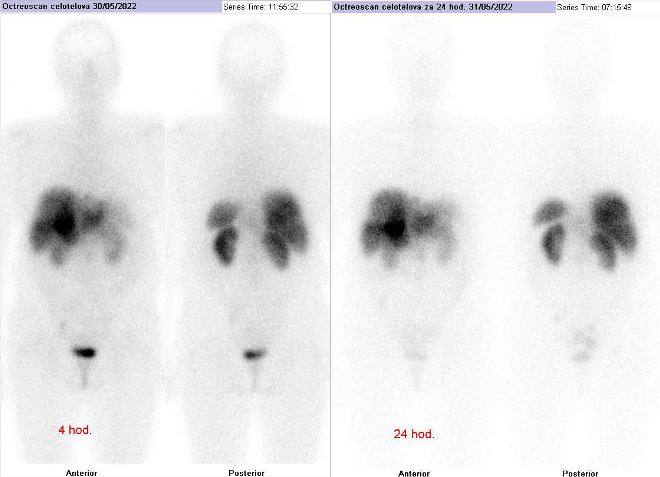

Scintigrafie Octreoscanem

I. v. jsme aplikovali 190 MBq analogu somatostatinu značeného 111In

(přípravek OctreoScan firmy Curium Netherlands B.V.) a provedli pomocí hybridní tomografické scintilační kamery Symbia T2 firmy Siemens opatřené kolimátory pro střední energie planární celotělovou scintigrafii a cílenou tomografickou scintigrafii (SPECT) břicha a pánve kombinovanou s CT.

/ Obr. č. 1: Celotělová scintigrafie v přední a zadní projekci 4 (vlevo) a 24 hod. (vpravo) po aplikaci OctreoScanu.

/

Pozorujeme patologické ložisko zvýšené depozice radiofarmaka v segmentu S4 pravého jaterního laloku, ve dvou uzlinách – jedné nad bránicí a druhé pod levým jaterním lalokem a v pánvi na rozhraní levé kosti kyčelní a kosti křížové, nález svědčí pro tkáň se zvýšenou denzitou somatostatinových receptorů.

Závěr:

U 68leté ženy s neuroendokrinním tumorem nejasného primárního zdroje prokazujeme generalizaci v játrech, uzlinách a skeletu.